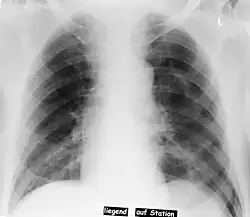

| Pneumothorax left sided | |

| Differential diagnosis | pneumothorax |

In radiology, the deep sulcus sign on a supine chest radiograph is an indirect indicator of a pneumothorax.[1][2] In a supine film, it appears as a deep, lucent, ipsilateral costophrenic angle[3] within the nondependent portions of the pleural space as opposed to the apex (of the lung) when the patient is upright. The costophrenic angle is abnormally deepened when the pleural air collects laterally, producing the deep sulcus sign.[4]